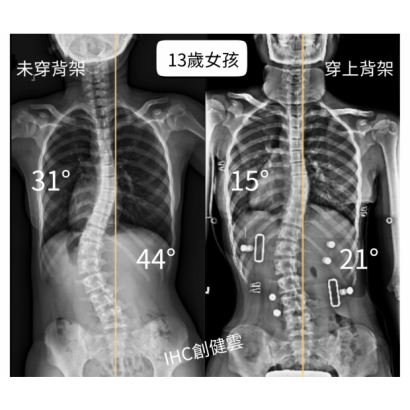

13歲脊椎側彎女孩,胸彎31度腰彎44度

原本在台大醫院就診,後醫師轉介,訂製【施羅斯側彎矯正背架】。

在專業評估與客製化設計完成後,背架的立即矯正效果:

胸彎由31度→15度,腰彎由44度→21度!

在背架支撐下,整體身形也呈現 更筆直、體態更平衡的狀態。